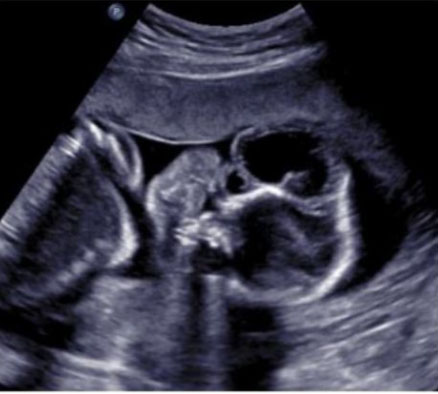

A routine fetal ultrasound assessment performed at 19 weeks’ gestation revealed right lateral encephalocele (Figure 1), large right cleft lip and palate with the defect expanding to the right eye socket, left lower extremity edema, and bilateral rocker-bottom feet (Figure 2, Figure 3, Figure 4). The patient underwent an amniocentesis at 20 weeks gestation that revealed normal male karyotype and normal microarray, without any maternal cell contamination. Repeat ultrasound at 23 weeks gestation showed previous anomalies with appearance of a thick right lateral amniotic band spanning the full length of the skull and facial defects as well as bilateral clenched fists (Figure 5). Fetal echocardiogram done at that time was without any evidence of structural cardiac abnormalities. She underwent extensive consultation in regard to ABS and outcomes, with plans for close follow-up. She presented at 26 weeks gestation for her scheduled growth scan reporting decreased fetal movement. She was diagnosed with intrauterine fetal demise measuring in the 9th percentile with an estimated fetal weight of 768 grams. She was admitted for induction of labor and went on to have an uncomplicated vaginal delivery. After delivery, fetal examination revealed profound midfacial deformities, brachydactyly, and placental adhesions. Placental pathology significant for a 20.7 cm long three vessel, peripherally inserted, umbilical cord with amnion constriction near placental insertion. Fetal membranes displayed features of amnion/chorion disruption as well as thickened bands of chorionic connective tissue and extraembryonic celom between the amnion and the chorion. These findings were somewhat difficult to fully discern due to the breakdown of fetal tissue after the intrauterine fetal demise.

Figure 1: (A and B) 3D views of facial cleft and lateral encephalocele.

Figure 2: Coronal view of facial cleft and lateral encephalocele.

Figure 3: Transverse view of amniotic band contact with fetal cranium.

Figure 4: Transverse view of lateral encephalocele.